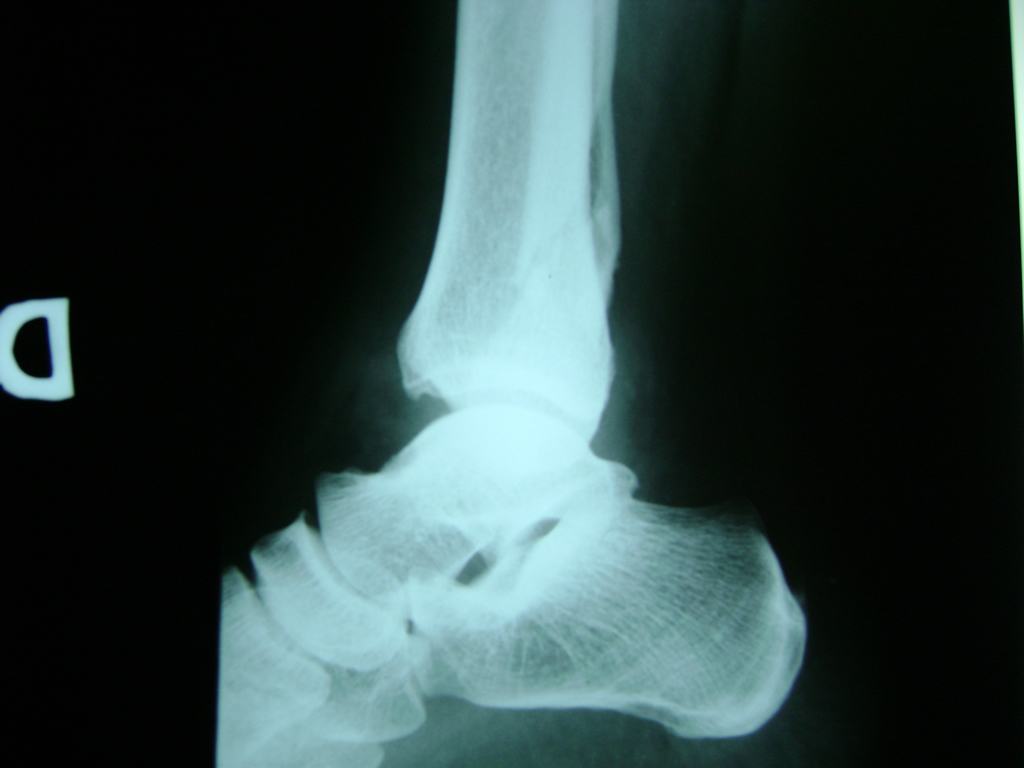

Una fractura de tobillo es la rotura de uno o más de los huesos del tobillo. Estas fracturas pueden ser:

Algunas fracturas de tobillo pueden requerir cirugía si:

- Los extremos de los huesos están desalineados entre sí (desplazados).

- La fractura se extiende hasta la articulación del tobillo (fractura intra-articular).

Cuando se necesita cirugía, es probable que esta implique el uso de clavijas de metal, tornillos o placas para sostener los huesos en su lugar mientras la fractura se consolida. Los elementos de soporte pueden ser temporales o permanentes.